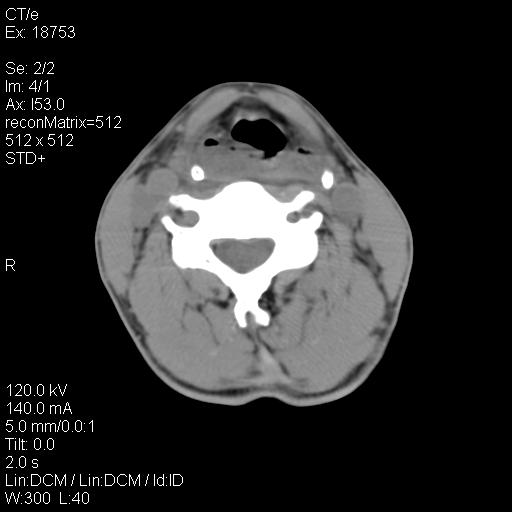

标题: CT21693:男 58岁 右侧咽部疼她2天余 PE:右侧扁桃体肿大 压痛 [打印本页]

标题: CT21693:男 58岁 右侧咽部疼她2天余 PE:右侧扁桃体肿大 压痛

右化脓性扁桃体炎症伴咽后壁脓肿形成.

1 弥漫性肿胀,与周围组织分界清晰,发病急,有明显症状,考虑急性炎症【wbc]

弥漫性肿胀,与周围组织分界不清,发病急,有明显症状,考虑:感染性病变!